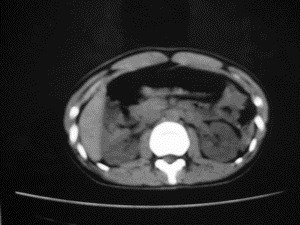

患者女,20岁,被车撞伤3小时,pe:全腹肌紧张,压痛反跳痛,以右上腹为著,肠鸣音减弱。有手术结果。![]() ![]() ![]() ![]() ![]() ![]() ![]() ![]() ![]() ![]() ![]() ![]() ![]() ![]() ![]() ![]() ![]() ![]() ![]() ![]() ![]() jiajie发言: ![]() 考虑空腔脏器穿孔。 dyqct发言:考虑:1、肝左叶外侧段断裂伤伴少量腹血。2、空腔脏器穿孔。 fangzheng发言:仅见腹腔内游离气体,提示空腔脏器穿孔。 guoke发言:胃内密度增高,肠腔内充满气体,考虑肠腔破裂出血 mmg94发言:胃后壁见一增厚软组织密度影,肝左叶前见游离气体影,左腹腔内局部肠管壁、系膜增厚。并见类圆形软组织。以上征象提示消化道管腔破裂,小肠、肠系膜挫裂伤,腹腔血肿形成。 拾荒者发言:肝实质密度不均匀,胃内见不均匀高密度影。考虑:肝挫裂伤,胃内应激性溃疡出血。 守望可可西里发言: 以下是引用jiajie在2006-6-20 15:49:00的发言:[br] [br][br]考虑空腔脏器穿孔。jiajie老师,我鼓起了很大的勇气才决定给您唱个反调儿,如果我错了,请您一定给我指出来,谢谢您了。我反复看了解剖图谱,觉得您所说的“考虑空腔脏器穿孔”上图所用箭头标明的不是游离气体。请您看以下几幅图片: ![]() ![]() ![]() ![]() ![]() ![]() ![]() ![]() 再请您看向医生老师发表的解剖图谱3幅 ![]() ![]() ![]() 这以下几幅图,我认为是肝包膜下积血。不过,说实在话,我没有发现有明显的肝挫裂伤。不对的地方请您一定指出来,再次感谢您了,jiajie 老师! ![]() ![]() ![]() ![]() 这下面几幅图片,我认为有明显的左中上腹部小肠损伤。 ![]() ![]() ![]() ![]() ![]() ![]() ![]() ![]() jiajie 老师,估计我说的是错误的,但我实在闹不明白,请您一定不要笑话我,并指出我的错误,以便于我减少工作中的失误。再次感谢您了,jiajie 老师! 至于胃内的不均匀高密度,我认为拾荒者战友说的有道理,胃内应激性溃疡出血和胃内容物混合所致。 手术结果:左肝叶(iv段)前缘长约8cm挫裂伤口,舌叶根部下< |